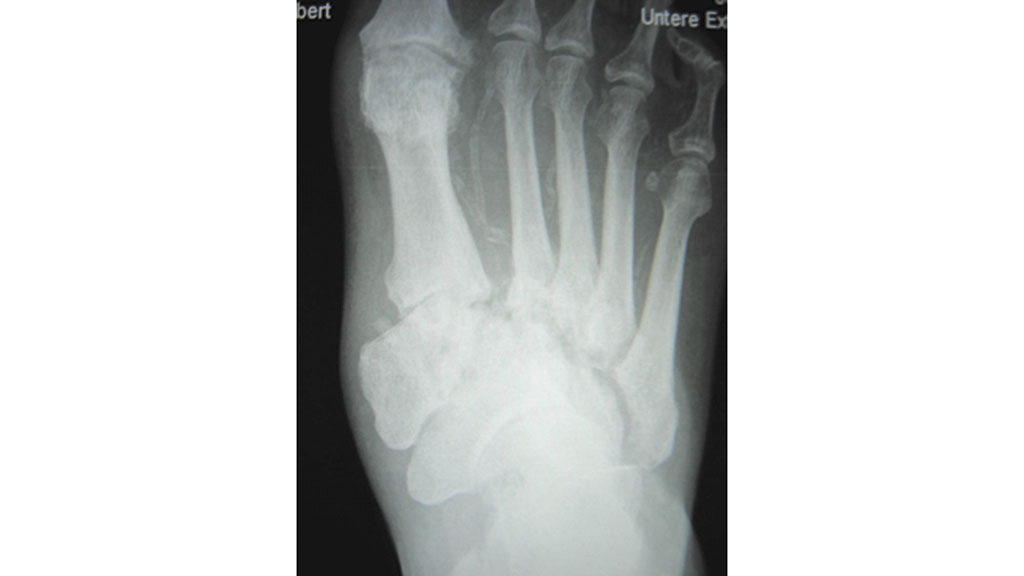

Die Diagnostik des Charcotfußes wird erschwert durch unspezifische Symptome mit schmerzfreier Schwellung, Rötung sowie Hyperthermie und erfolgt vorrangig durch das konventionelle Röntgen. Hier lassen sich anhand des Röntgenbefundes im Anfangsstadium Knochenauflösungen im Basisbereich des 1. und 2. Strahls nachweisen, die eine typische Deviation (Auseinanderweichung) zueinander zur Folge haben (Abb. 6).

Aber auch im Mittelfuß/Fußwurzelbereich sind Osteonekrosen darstellbar. Auch typische Spontanfrakturen im Mittelfußbereich sowie Luxationen im Lisfranc- und Chopartbereich treten auf.